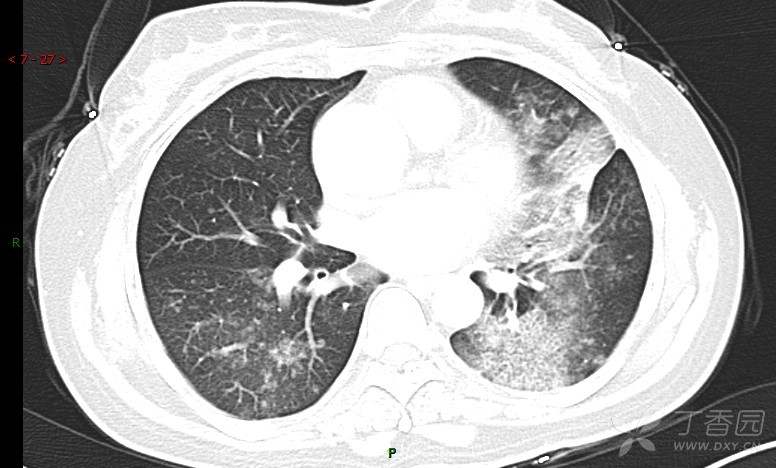

腺泡结节影,蜂窝征,这些都在提示……(病例3连发,附其他2例链接,病理已公布)

咳嗽1年余,加重7天。

患者于1年余前始受凉后出现咳嗽,多为干咳,未在意,未到医院就诊。近3月患者出现咳痰,多为黄色粘痰,量大,伴乏力,偶有头晕、心慌,无发热、胸痛、憋喘,无低热、盗汗、咯血、胸痛,无头痛,无恶心、呕吐、腹痛、腹泻,无尿频、尿急、尿痛,在当地诊所给予抗感染等对症支持治疗(具体药物及剂量不详),症状仍时有反复。患者于1月余前到外院就诊,行胸部CT提示双肺炎症,左肺重,考虑为“间质性肺炎”,给予“左氧氟沙星、利巴韦林、头孢哌酮舒巴坦钠注射液”治疗,复查胸部CT示病灶吸收不理想,后出院继续于诊所对症治疗(具体药物及剂量不详),效果欠佳。7天前患者无明显诱因出现上述症状加重,为求进一步诊治,特来我院就诊,我院门诊以“肺炎(重症)?”收入留观室,留观室给予“盐酸莫西沙星氯化钠”等对症治疗后,今日转入我科。患者自发病以来,神志清,精神差,饮食正常,睡眠增多,大小便正常,体重近3月减轻5公斤余。